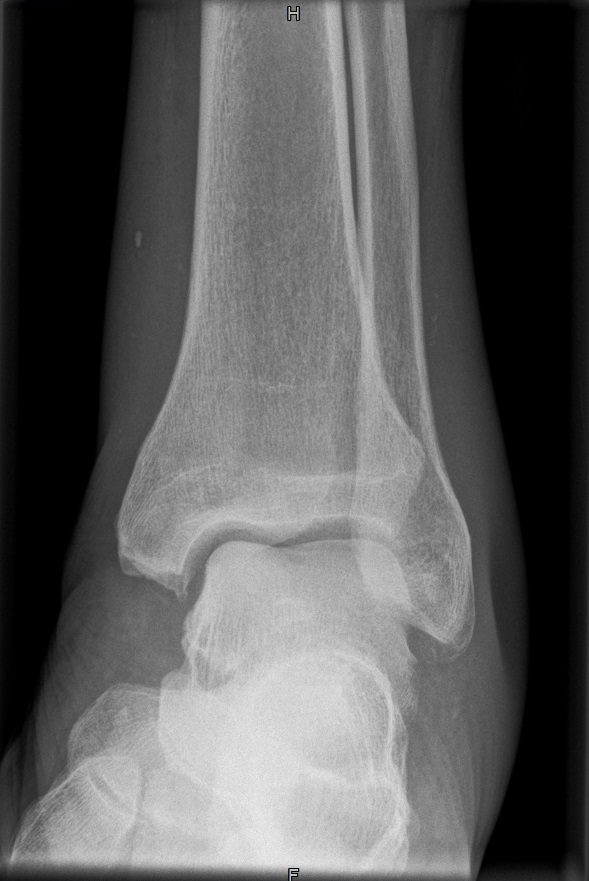

OSG a.p.

Fehler

Leichte Außenrotation des Fußes. Die laterale Kante der distalen Tibia springt besonders markant vor und verdeckt teilweise den Schaft der Fibula.

Abhilfe

Fuß weiter nach innen drehen lassen, bis beide Malleolen auf einer Höhe parallel zum Film stehen.